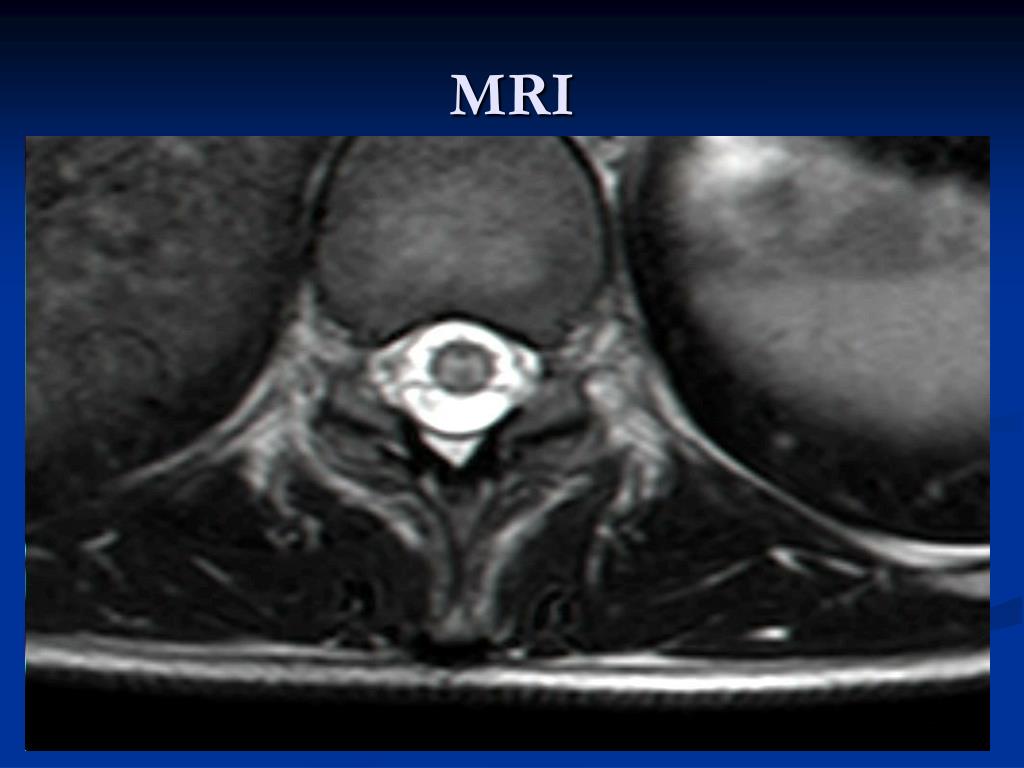

4. MRI

5. MRI

6. MRI

15. WNV MYELITIS = WNV POLIOMYELITIS-LIKE SYNDROME Acute and asymmetric flaccid paralysis occurs in about 10% of the patients who are hospitalized for WNV infection. Neurological lesion is localize in the anterior horn motor neurons. CSF-moderate pleocytosis of few hundred lymphocytes, protein is moderately elevated , glucose is normal. MRI of the spinal cord – high signal intensity on T2-weighted scans in anterior horns .